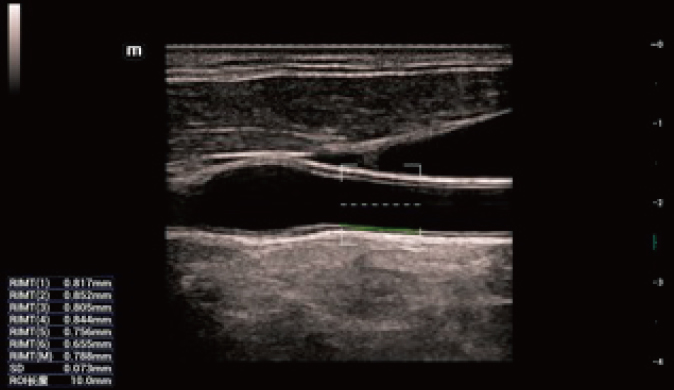

Für die Ultraschalltechnologie stellt die ZST+-Plattform einen bedeutenden Fortschritt dar, da sie statt der herkömmlichen Strahlformung die Kanaldatenverarbeitung verwendet. Diese bahnbrechende Innovation löst übliche Zielkonflikte zwischen räumlicher Auflösung, zeitlicher Auflösung und Homogenität des Gewebes auf, woraus sich eine beispiellose Bildqualität ergibt, die den Weg frei macht für unendlich viele Bildgebungslösungen.

Das Resona I8 weist vielfältige klinische Lösungen auf, die speziell für den jeweiligen Anwendungsbereich entwickelt wurden. Die Technologie baut auf einem tiefgreifenden Verständnis verschiedener klinischer Szenarien auf und bietet eine umfassende Serie fortschrittlicher Diagnoseinstrumente, beispiellose Intelligenz und präzise Analysen zur Verbesserung von Diagnosesicherheit, Qualitätskontrolle und Scaneffizienz.